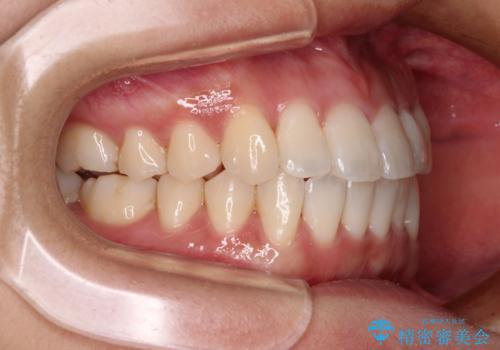

捻れた前歯をできるだけ短期間で 表側のワイヤー矯正

日々前歯の捻れが解消されていくので、歯の動きを楽しみながら矯正治療を進めることができました。